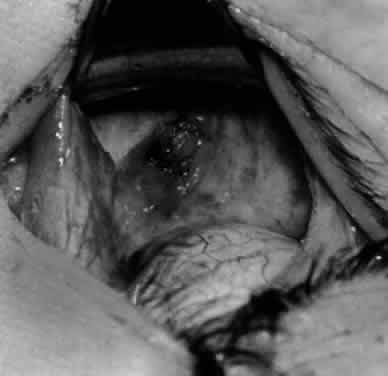

Fig. 3. The eye is retracted superonasally with the 4-0 silk traction suture. The suture is attached to the drapes with a hemostat. A Stevens hook is placed along the inferior border of the lateral rectus muscle and drawn temporally. A von Graefe hook is placed within the incision and drawn inferotemporally to expose the inferior oblique muscle.

Fig. 4. A stiff iris repositor can be placed against the sclera to depress the sclera and enhance the view of the inferior oblique muscle. The inferior temporal vortex vein adjacent to the Stevens hook is retracting tissue along the inferior border of the lateral rectus muscle. The second Stevens hook is pointing to the inferior oblique muscle.